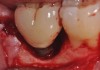

Fig 3. Clinical view of a mandibular left first molar in an 84-year-old patient with a peri-implantitis lesion. The implant had been healthy for the previous 5.5 years.

Figure 3